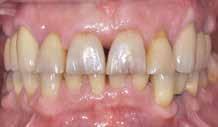

Den kliniske undersøgelse viser harmoniske ekstraorale sagittale forhold med skeletalt dybt bid (Fig. 1A, D). Hendes smil er alderssvarende med en eksponering på 8/10 af overkæbeincisiverne, mens smilets bredde er smalt med synlige mørke laterale rum (Fig. 1D). Underkæbeincisiverne er synlige under tale. Der ses neutrale okklusale forhold ved hjørnetænderne og neutrale pladsforhold i overkæben, men udtalt trangstilling i underkæben især lokaliseret i regio 1-1 (Fig. 1C).

Sliddet klassificeres som grad 2 (moderat tandslid) på de centrale incisiver i overkæbe og underkæbe. Det kan anses som patologisk, da det er atypisk for patientens alder, giver anledning til smerte/ubehag, og giver patienten et æstetisk problem. Der ses infraktioner af overkæbeincisiverne. Der ses endvidere en udtalt Spee-kurve i underkæben og ingen interincisal afstøtning på 2-2 med let ganepåbidning.

Røntgenanalyse viser fravær af -6 samt et velholdt tandsæt uden tegn på sygdom. Profilrøntgenbilledet viser et skeletalt

dybt bid, men normal inklination af fortænder i over- og underkæbe (Fig. 1B).